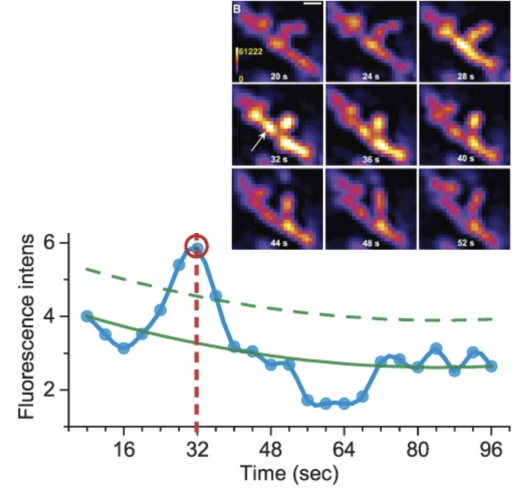

Galaxy Image Analysis: Capturing Mitoflashes

Workflow: https://usegalaxy.eu/u/bmcv/w/capturing-mitoflashes

Paper: https://doi.org/10.1097/j.pain.0000000000002642